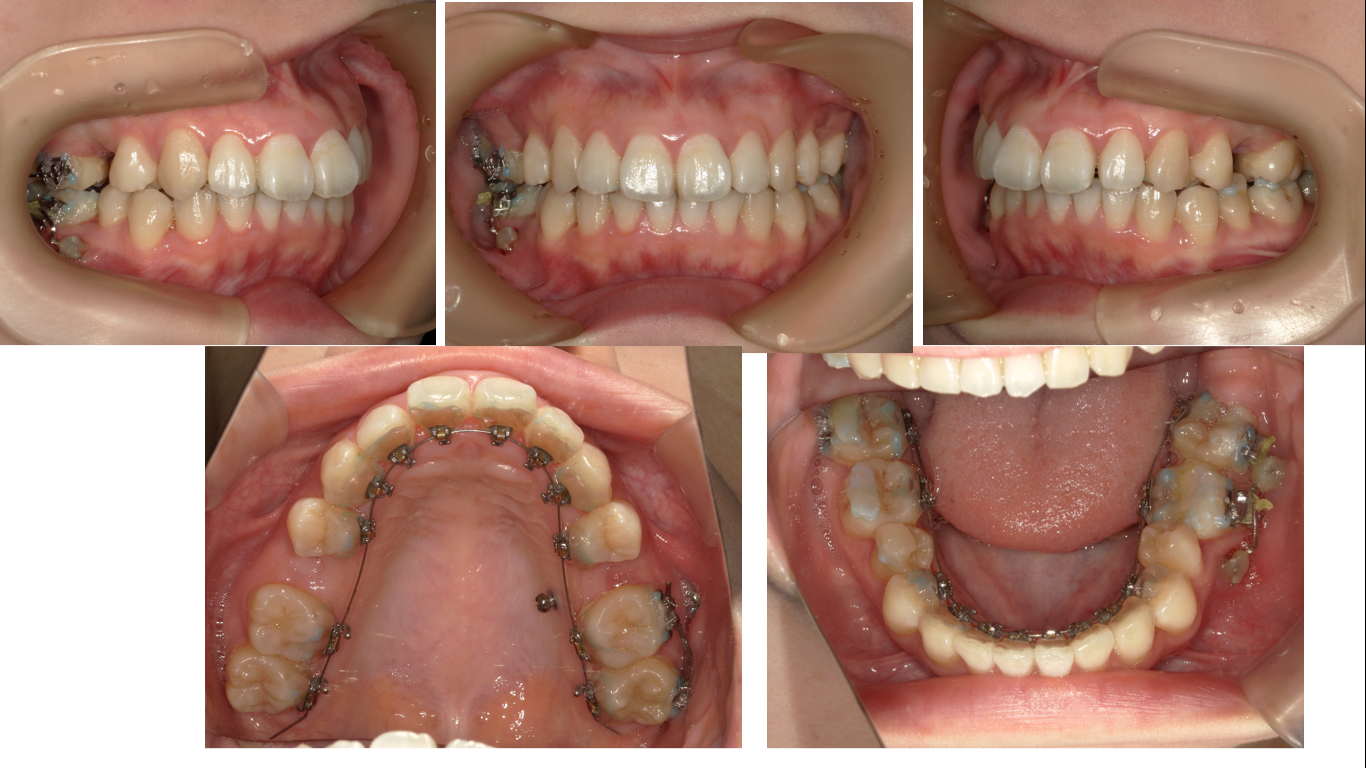

右上7番が鋏状咬合です。これを治すのに6か月かかりました。

6番の構い合わせが咬頭対咬頭のかみ合わせにみえますが、そう見えるだけです。実際は2級の理想的な大臼歯のかみ合わせとなっています。

下顎の左右5番は抜歯前提でIPRを行いました。が、そのまま残すことになりました。